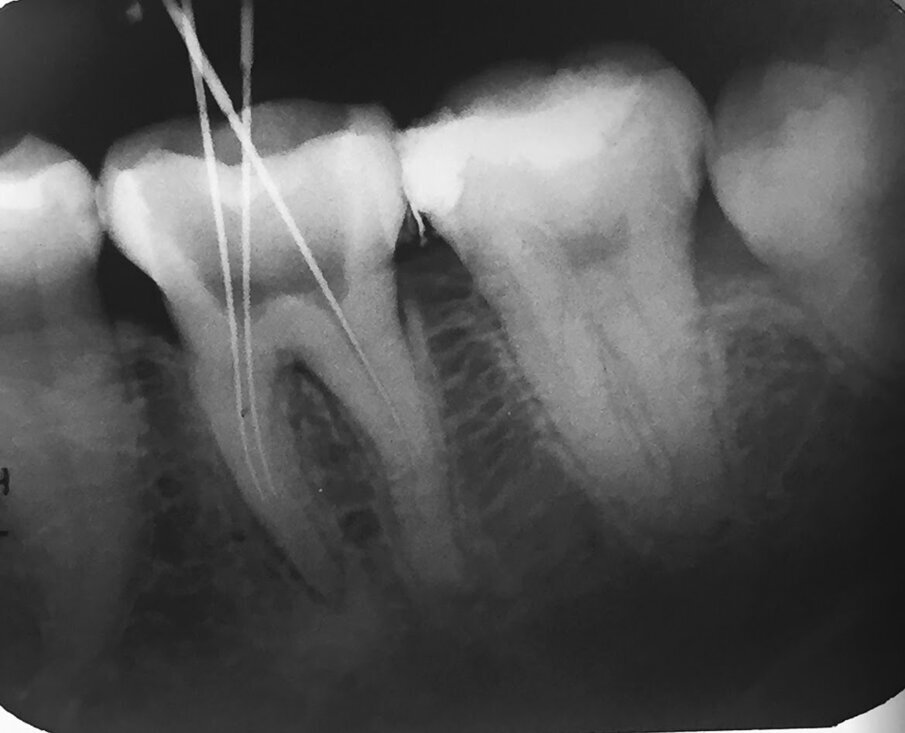

Dr Margaret Tui, a clinician based in the Philippines, agrees that the increased fatigue resistance and strong flexibility of both HyFlex systems allowed her to manage an S-shaped case more easily. At a recent COLTENE Train the Trainer event, she presented a mandibular first molar case with four canals that was referred to her by another dentist who could not negotiate the canal owing to its difficult anatomy. After utilising the crown-down technique and the HyFlex CM files to flare the coronal third of the distobuccal and distolingual canals, Tui then continued to use HyFlex EDM to negotiate the mesiobuccal and mesiolingual canals, as she had discovered a slight curvature in the middle third of the canals. As for the S-shaped distobuccal and distolingual canal, she continued with the Hyflex CM files. Post obturation radiograph showed properly shaped canals with proper healing.

Fig. 6: Dr Margaret Tiu presented a mandibular first molar case with four canals. She used a combination of HyFlex CM and HyFlex EDM to properly shape the canals.

Radiograph from referred dentist